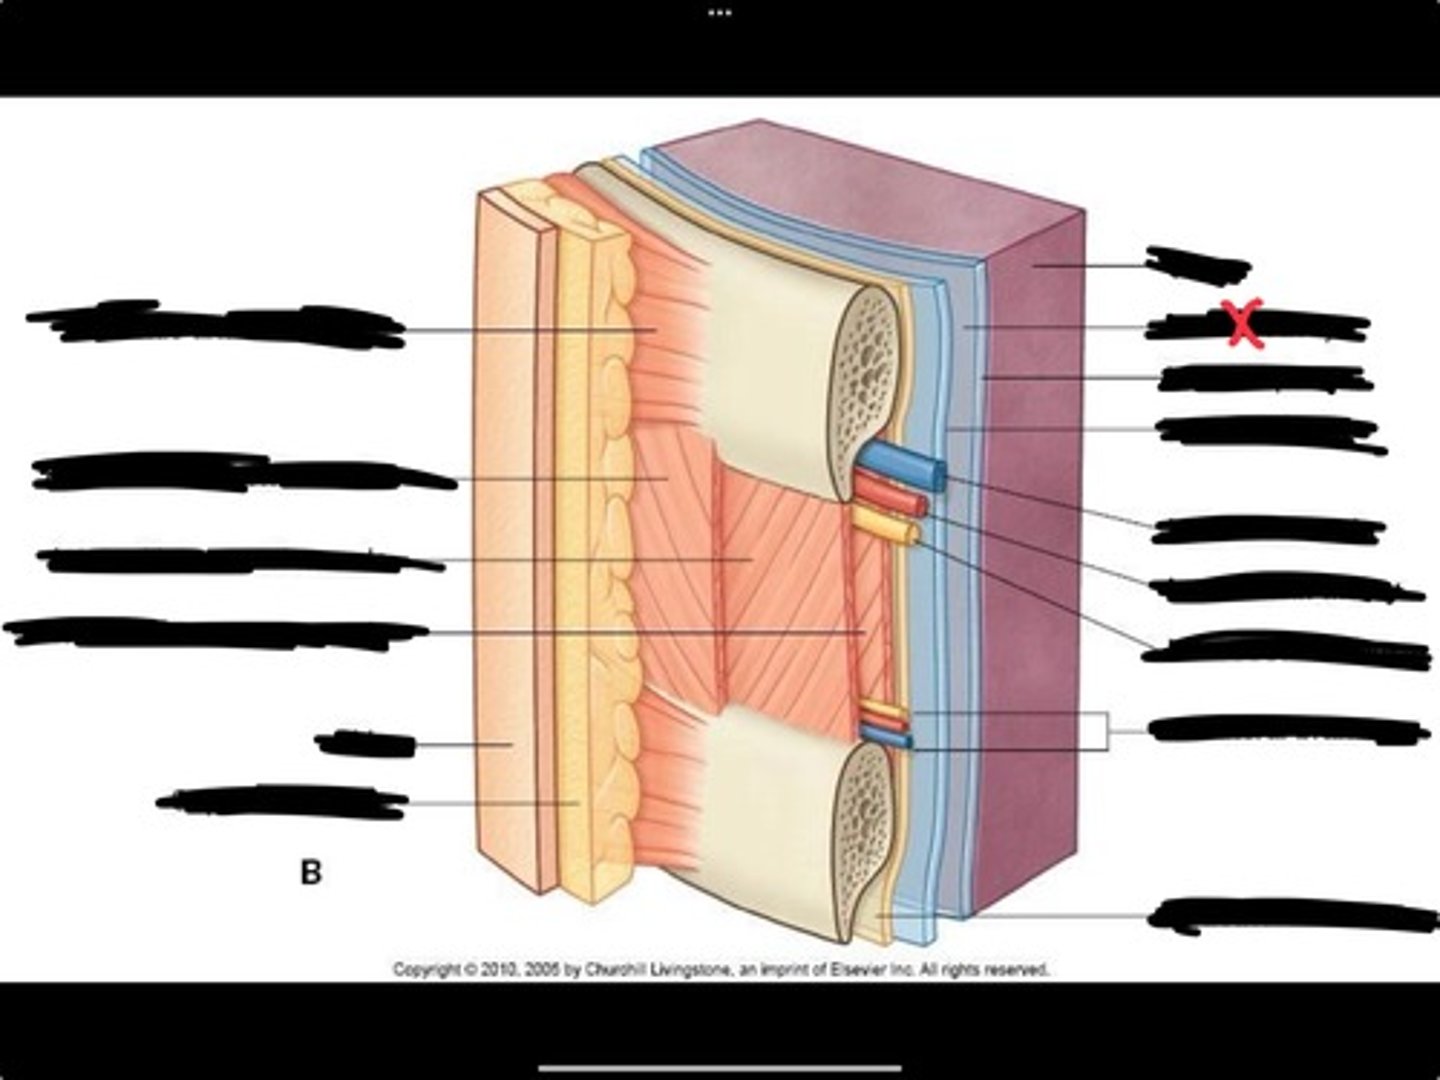

Innermost intercostal muscle

Skin

Internal intercostal muscle

External intercostal muscle

Serratus anterior muscle

Lung

Pleural cavity

Visceral pleura

Parietal cavity

Intercostal vein

Intercostal artery

Collateral branches

Intercostal nerve

Endothoracic fascia